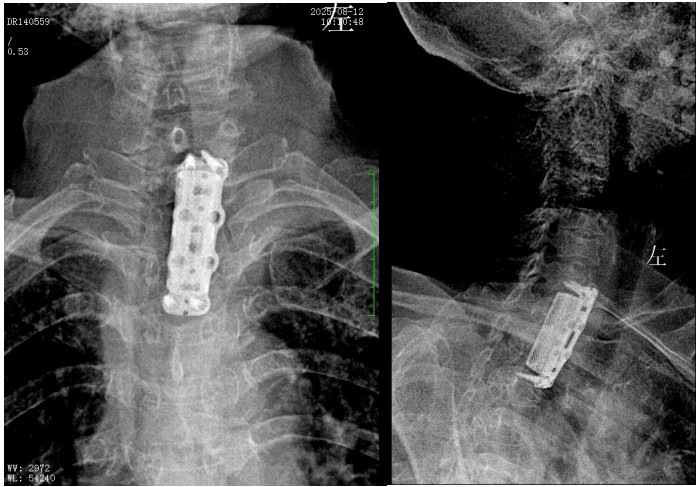

錢軍博士組織團(tuán)隊(duì)進(jìn)行了詳盡的術(shù)前討論,充分的術(shù)前準(zhǔn)備后,于8月10日為患者實(shí)施了“前路病灶清除、人工椎體植入、植骨融合內(nèi)固定術(shù)”。順利完成了徹底清除病灶,椎管減壓解除脊髓壓迫,矯正后凸畸形,重建脊柱穩(wěn)定性的手術(shù)目標(biāo)。

術(shù)后,脊柱外科醫(yī)護(hù)團(tuán)隊(duì)為病人制定了快速康復(fù)方案,經(jīng)過精心治療與護(hù)理,李奶奶訴胸背部、雙上肢的疼痛癥狀較前明顯好轉(zhuǎn),晚上終于能睡個安穩(wěn)覺了。兩周后,李奶奶恢復(fù)良好,現(xiàn)已順利出院。